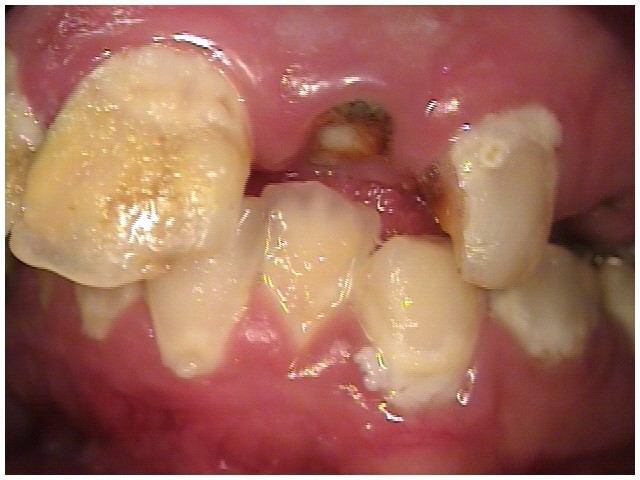

Often, the most visually striking manifestation of long-term meth use—known as “meth mouth”—is caused by the lack of saliva combined with an increase in soda drinking and extremely poor oral hygiene. This typically leads to meth abusers experiencing a large amount of caries. Decay begins with occlusal and facial caries and progresses rapidly, decaying to the bone level and often leaving only roots (Figure 1 through Figure 3).16

In Figure 7 through Figure 9, the young woman shown had many adverse childhood experiences and was given methamphetamine by an adult when she was 14 years old. She also had her first child at that age, and then had three more children while addicted to meth, though she was only able to retain custody of one of her children. In addition to alcohol, she used meth for 15 years. Her only prosthetic option was extraction of all of her remaining teeth and subsequent placement of complete dentures.

Fig 7 through Fig 9. This young patient’s only prosthetic option was extraction of all remaining teeth and subsequent placement of complete dentures.

Figure 7

Figure 8

Figure 9